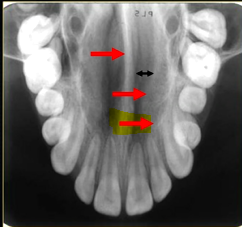

what does this anterior periapical graph show?

oval radiolucent area between the central incisors - is it Infront of the teeth (buccally?) or is it behind them? - you can’t tell radiographically

but its shape and position is compatible with the palatally positioned with the nasopalatine formaina

more posteriorly - radiopacities indicate the nasal septum and floor of the nose

dense, thin , white line in the middle of the image is the nasal septum

less dense opacity is caused by the

inferior nasal concha

radiolucency - nasal septum

lateral wall of the nose

maxillary air sinus

mid-palatal suture

this increased radiopacity is caused by the soft tissues at the tip of the nose - shadow - dense tissue